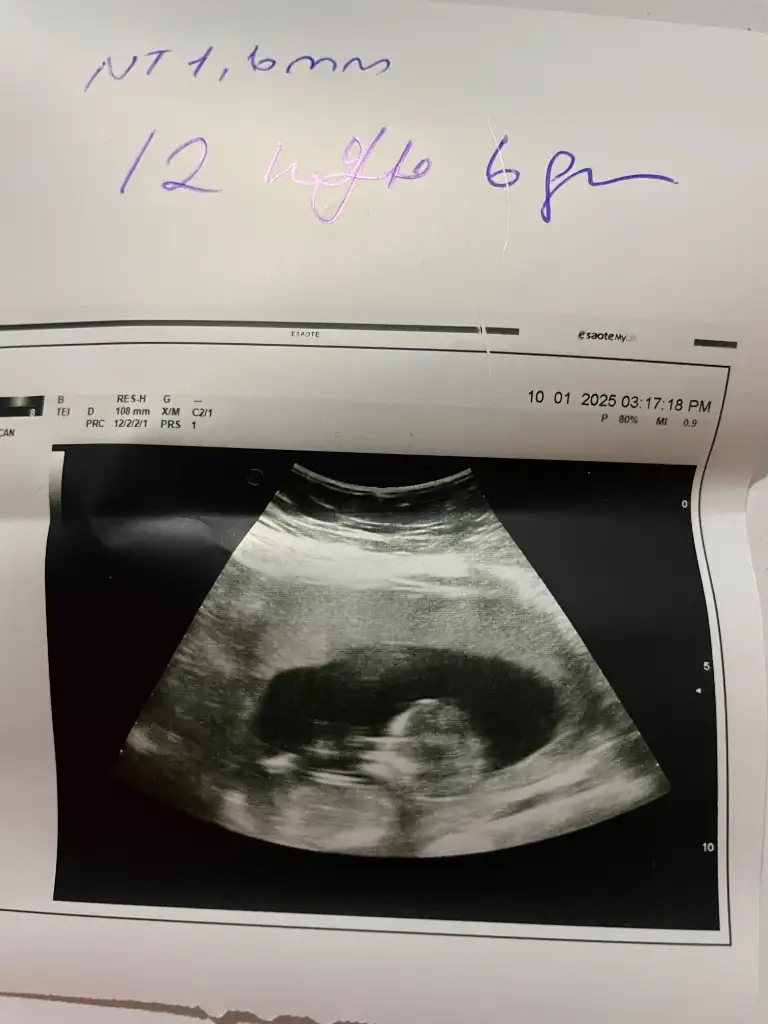

Merhaba 11+2 haftalık ultrason görüntüsü cinsiyet yorumlayabilir misiniz rica etsem?

Eki Görüntüle 3531617

Eki Görüntüle 3531618

Çok net görünüyor erkek. Hayırlı olsun

Sizinki de erkek gibi görünüyor. Allah gönlünüze göre versinBana da yorum yapar mısınız

Emin olamadım bunda kız gibi ama gönlünüzce olsun inşallahCanım benimkinede bakar mısın